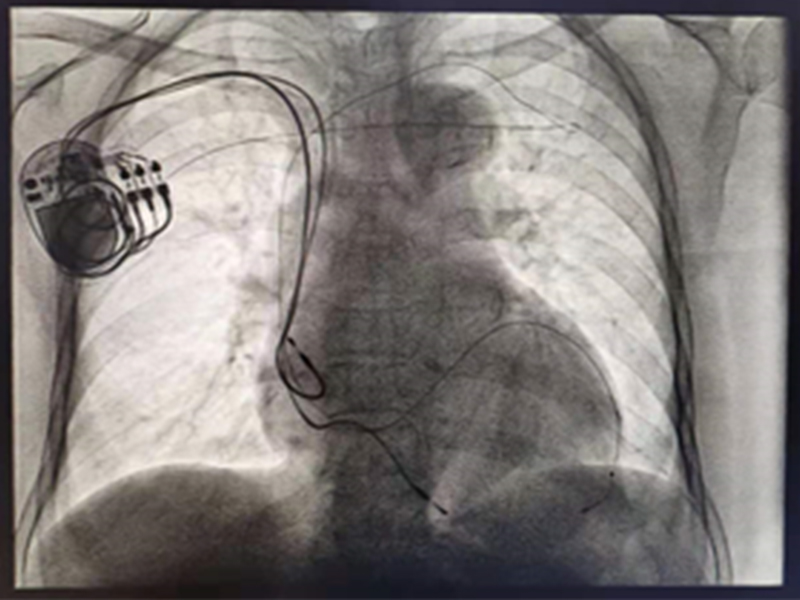

72 12 ICU CRT 2 CRT

15% CRT( )